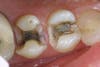

Mercury (as in a thermometer) expands and contracts with change in temperature, every time you consume anything hot or cold. This amalgam filling is sitting in a tooth that resembles glass or china. This chunk of metal then expands and contracts within this brittle tooth. So what do you think it will do to the tooth surrounding this material? That’s right, it will cause fractures. Fractures can break the tooth. How many of you have had a crown because your tooth broke but the filling was still intact?! Fractures also will leak, allowing bacteria to penetrate within, causing decay (cavities). The photos I have posted to this blog clearly show what we see when we remove the amalgam.